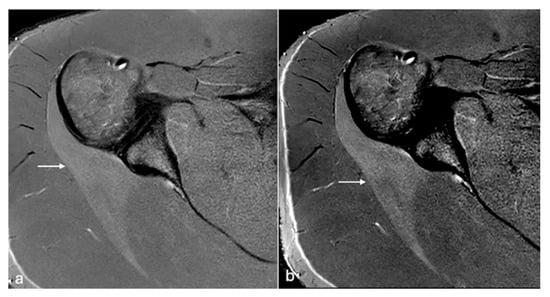

Figure 4. PDFS axial MR images of the right shoulder (a,b). Subtle early changes in muscle oedema in the infraspinatus muscle (arrow) are better detected on the image with modified windowing (b) when compared to default windowing (a). W/L of image (a)—1820/972, (b)—931/936.